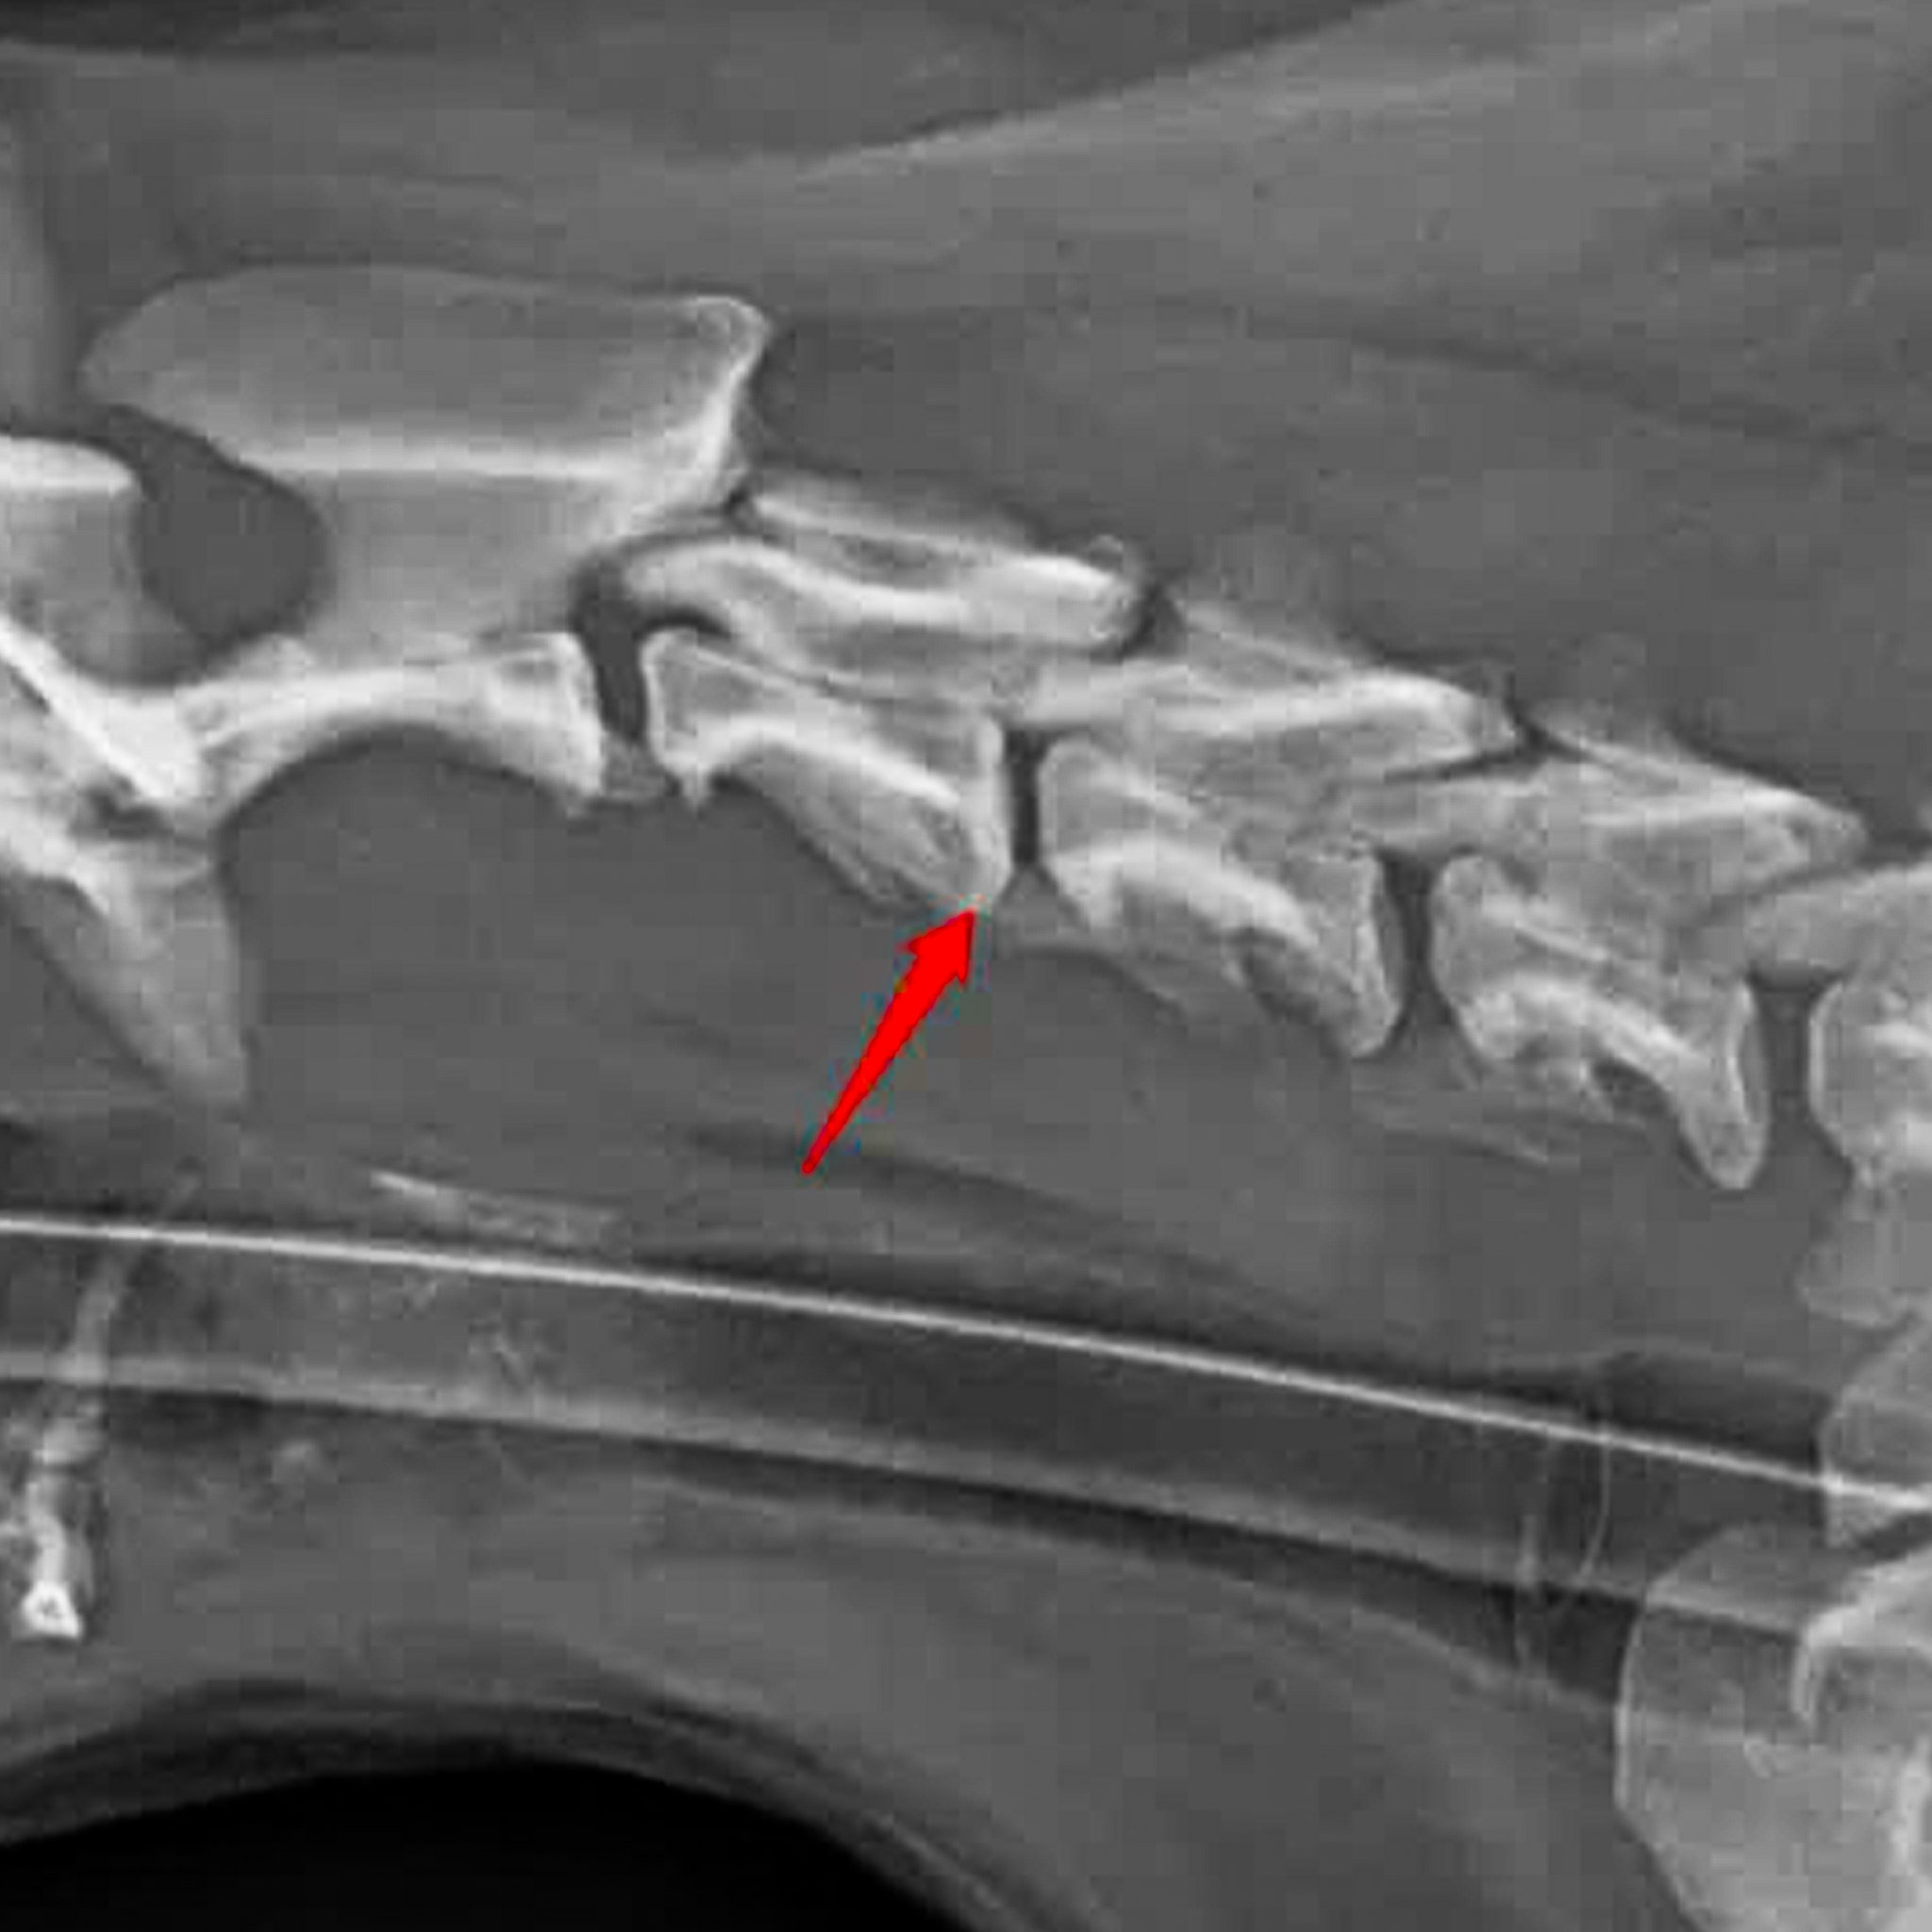

Dịch vụ phẫu thuật cố định cột sống và thoát vị đĩa đệm ở chó mèo – Chẩn đoán và điều trị bệnh lý đĩa đệm C3 – C4 ở bạn chó Bomi

Báo cáo ca lâm sàng: Thoát vị đĩa đệm C3 - C4 ở chó Bomi